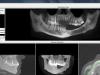

GBean Опубликовано 6 декабря, 2012 Автор Поделиться Опубликовано 6 декабря, 2012 Спасибо всем большое.КТ полностью выложена тут: http://rusfolder.com/33981929 ~ 180 Mb В архиве и программа установки - Ez3D2009Отдельно папка с файлами dct****.dcm лежит тут: http://rusfolder.com/33981982 ~ 45 MbКТ делалась ради 6-ки, но 8-ку видно.Спасибо еще раз за ваше время. Ссылка на комментарий

IvanK Опубликовано 7 декабря, 2012 Поделиться Опубликовано 7 декабря, 2012 Спасибо всем большое.КТ полностью выложена тут: http://rusfolder.com/33981929 ~ 180 Mb В архиве и программа установки - Ez3D2009Отдельно папка с файлами dct****.dcm лежит тут: http://rusfolder.com/33981982 ~ 45 MbКТ делалась ради 6-ки, но 8-ку видно.Спасибо еще раз за ваше время. Сделайте скриншоты. Ссылка на комментарий